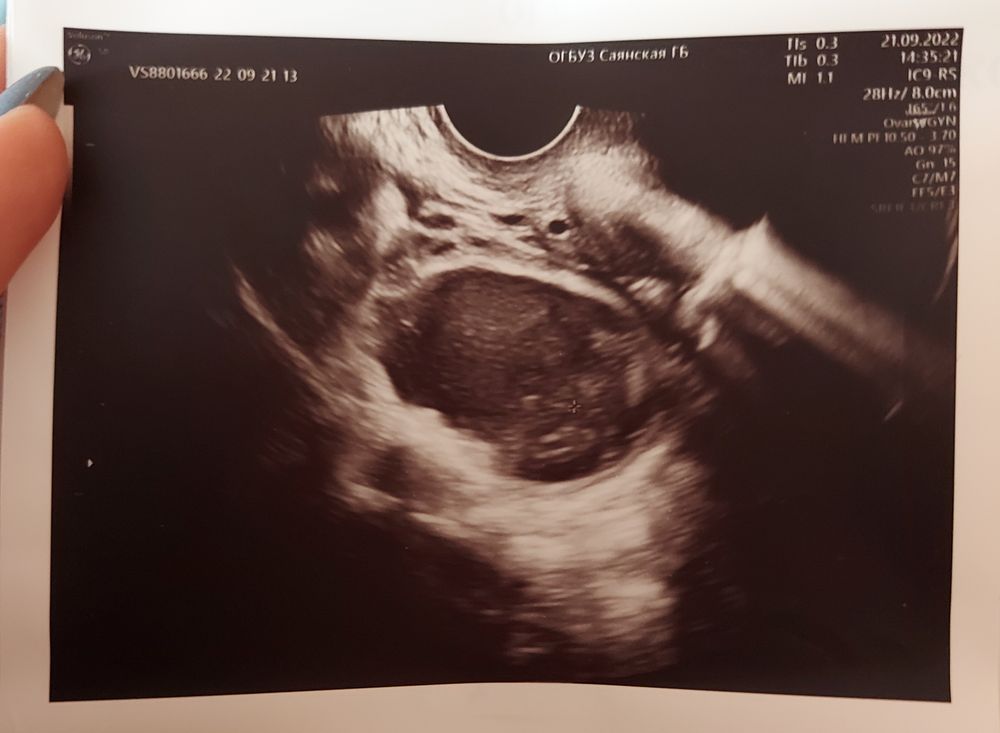

Помогите разглядеть🤣

Из всего, что тут понятно - это плодное яйцо 😅 нафиг они вообще такие снимки дают, где ничего не видно?

Вообще не понимаю, что на этом фото 😃 если бы вы не написали, что там эмбрион , я бы даже не поняла, на обычное УЗИ матки похоже 😃 Узист не заморачивался с фотографией на память

Викуся, ну вот большой овал - это плодное, просто в масштабе🤣

renaisse , наверное они переборщили с масштабом 😀

Фотка реально от балды сделана